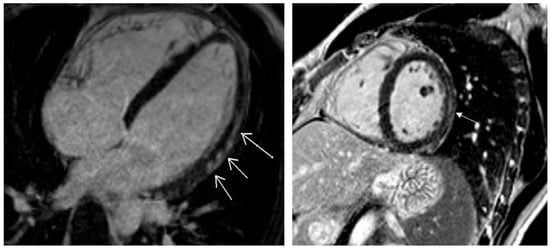

| LGE positive, n (%) | 29 (43.3) |

| LGE in ≥3 segments, n (%) | 25 (37.3) |

| LGE layers, n (%) | |

| epi | 11 (37.9) |

| epi or mid | 12 (41.4) |

| mid | 6 (20.7) |

| Total abnormal, n (%) | 39 (58.2) |

| Pericarditis, n (%) | 8 (12.5) |